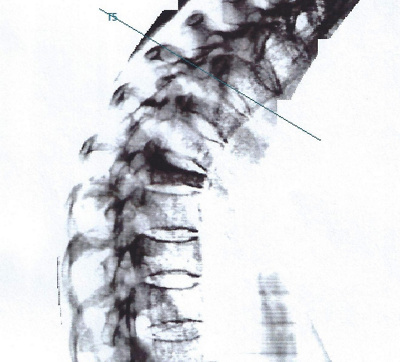

Rückenschmerzen

Am Rücken können unterschiedliche Strukturen zu Schmerzen führen. Um Rückenschmerzen gezielt individuell behandeln zu können, werden neben der genauen Befragung (Anamnese) und der klinischen Untersuchung bildgebende Verfahren wie Röntgen oder MRT/MRI (Magnetresonanztomographie) eingesetzt. Zur Schmerzkontrolle sind gezielte Infiltrationen unter Röntgen, Ultraschall und CT (Computertomographie) möglich. Neben der Schmerzkontrolle mittels Infiltration/Medikamenten ist für einen langfristigen Erfolg meistens individuelles Training wichtig.